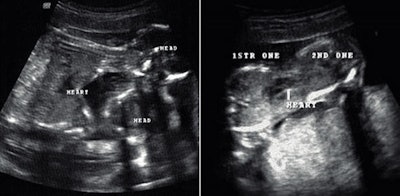

A Voluson 730 ultrasound machine from GE Healthcare (Waukesha, WI) was used. The transabdominal ultrasound was performed, and two conjoined female fetuses were detected; each fetus was with a single head and a pair of arms and legs. The twins were joined at the lower chest and the upper abdomen. Only one functional fetal heart was observed centrally between both the fetuses with slight tendency toward one of the fetuses (figures 1 and 2). Single anterior placenta was seen with the umbilical cord and a normal amount of fluid. The color Doppler study showed two aortic arches emerging from the single functional heart (figure 2). On the basis of these findings, a diagnosis of dicephalic thoraco-omphalopagus conjoined twins was made (figure 3).